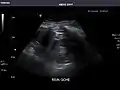

Renal ultrasonography

Ultrasound scan of a kidney (right side)

Ultrasonography of the kidneys is essential in the diagnosis and management of kidney-related diseases. The kidneys are easily examined, and most pathological changes in the kidneys are distinguishable with ultrasound.[7]